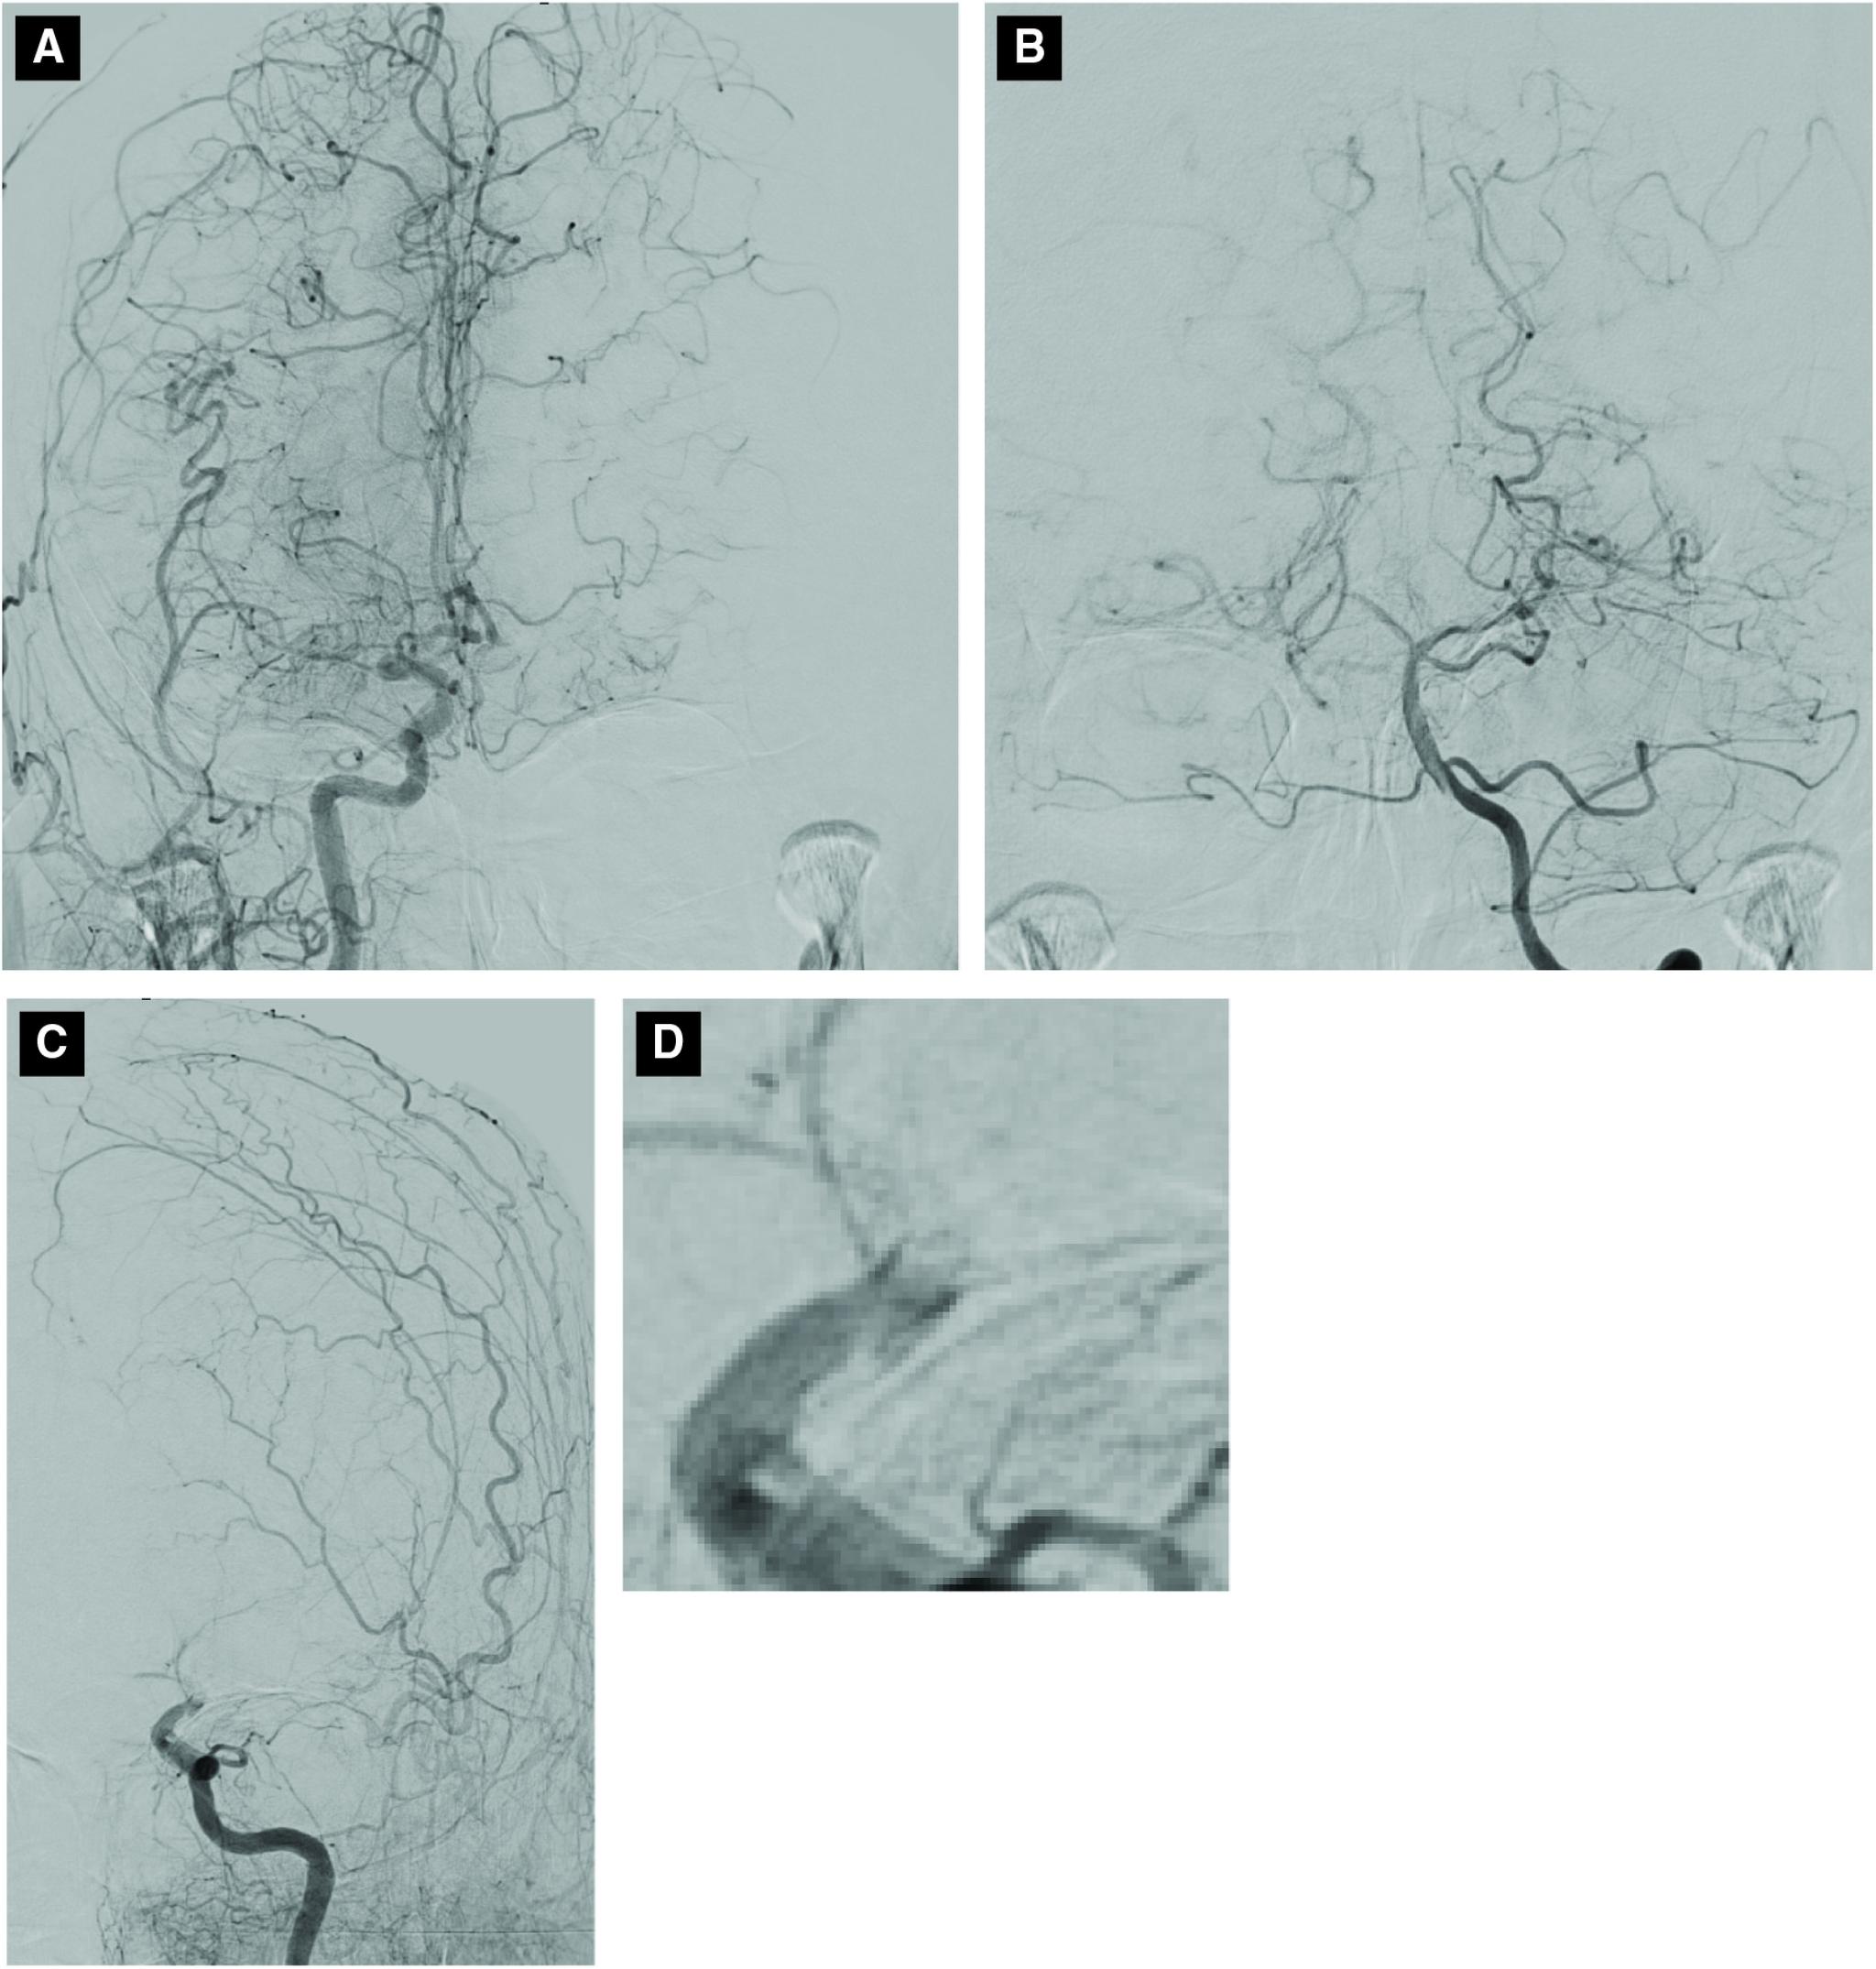

CASE PRESENTATION

A 73-year-old woman was diagnosed with moyamoya disease by asymptomatic right middle cerebral artery occlusion at 59 years of age. The patient was transported for stroke symptoms. Magnetic resonance imaging (MRI) demonstrated left terminal internal carotid artery occlusion and low-intensity signal on T2*-weighted imaging at the occlusion site. Alteplase was administered and endovascular treatment was subsequently performed. A small-diameter microcatheter was guided to the distal end of the occlusion and angiography after deployment of a stent retriever revealed irregular stenosis. Severe stenosis remained after thrombectomy, and balloon angioplasty was added. The treatment resulted in recanalization and good outcome.

一名73岁女性在59岁时因无症状性右侧大脑中动脉闭塞被诊断为烟雾病。该患者因中风症状被送来就诊。磁共振成像(MRI)显示左颈内动脉末端闭塞,闭塞部位在T2*加权成像上呈低强度信号。给予了阿替普酶并随后进行了血管内治疗。将一根小直径微导管引导至闭塞远端,在部署支架取栓器后进行血管造影显示不规则狭窄。取栓术后仍存在严重狭窄,遂加用球囊血管成形术。治疗导致血管再通且预后良好。